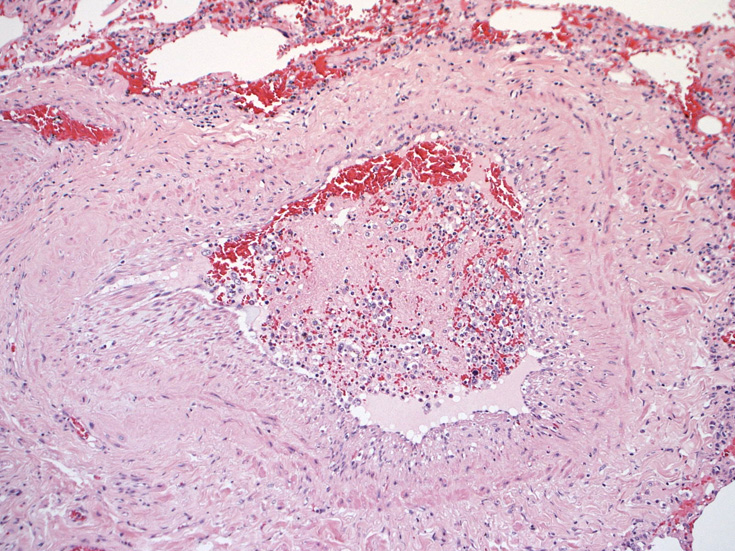

骨髄の組織所見

肺組織所見